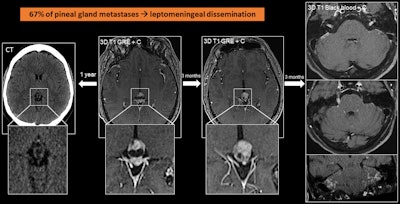

Pineal gland metastases occur in 0.4% to 3.8% of cancer patients, with the most common primaries occurring in the lung and breast. Most pineal metastases are asymptomatic, although they may clinically present with headache, encephalopathy, and hydrocephalus. Identifying pineal metastases is crucial, as they can lead to leptomeningeal dissemination, which occurs in up to 67% of cases, they added.

A 56-year-old man with lung cancer with pineal metastasis, which appears as a complex cystic lesion with a solid anterior pole. This finding, which was not present in a CT scan obtained a year earlier, progressed in the MRI scan after three months. In the following months, he developed leptomeningeal dissemination.

“Like pituitary metastases, they are not easy to differentiate from other lesions,” the researchers stated. “Suspect when there are new pineal lesions in patients with lung and breast cancer.”